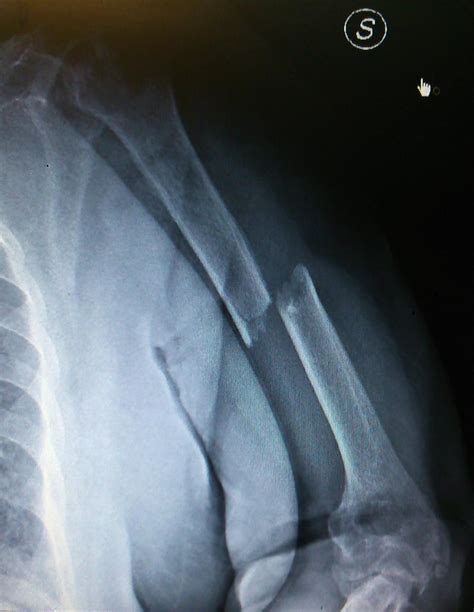

X-ray showing a humerus fracture

Medical professionals categorize a Left Humerus Fracture based on the specific location of the break. The humerus is anatomically divided into three main segments, each requiring different management strategies:

Furthermore, fractures are classified as either displaced (where the bone fragments have moved out of alignment) or non-displaced (where the bone is broken but remains in its proper position). The severity of the displacement often determines whether surgery is required.